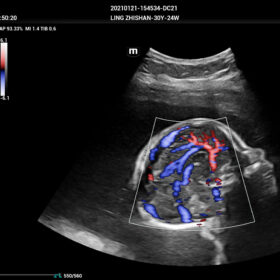

- HR-Flow Improving the hemodynamic presentation

- Smart Scene 3D – Full Stack smartness obstetric solution empowered by ZST+. Comprehensive 3D/4D OB imaging solution with comprehensive fetal parts coverage.